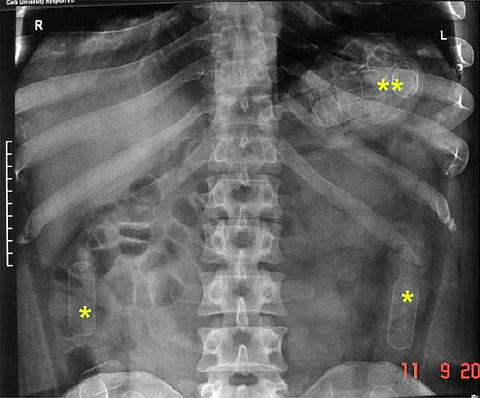

जे. जे. रुग्णालयात त्याचा एक्स-रे काढण्यात आला व सोनोग्राफी करण्यात आली. त्या वेळी त्याच्या पोटात मोठ्या प्रमाणात कॅप्सूल असल्याचे उघड झाले होते. डॉक्टरांनी पाच दिवस प्रयत्न करून त्याच्या पोटातून ५६ कॅप्सूल काढल्या. त्यात कोकेन असल्याचे निष्पन्न झाले. अधिकाऱ्यांनी जप्त केलेल्या ६०० ग्रॅम कोकेनची किंमत एक कोटी ८३ लाख रुपये असल्याचे एआययूच्या अधिकाऱ्यांनी सांगितले. अमेरिकेपर्यंत धागेदोरे पोहोचलेल्या या प्रकरणात मोठ्या आंतरराष्ट्रीय टोळीचा हात असल्याचा पोलिसांना संशय आहे.